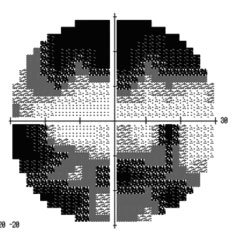

ビーライン社製 視野解析ソフトHfaFilesによる解析

カールツアイス社製ハンフリー視野計による視野検査結果